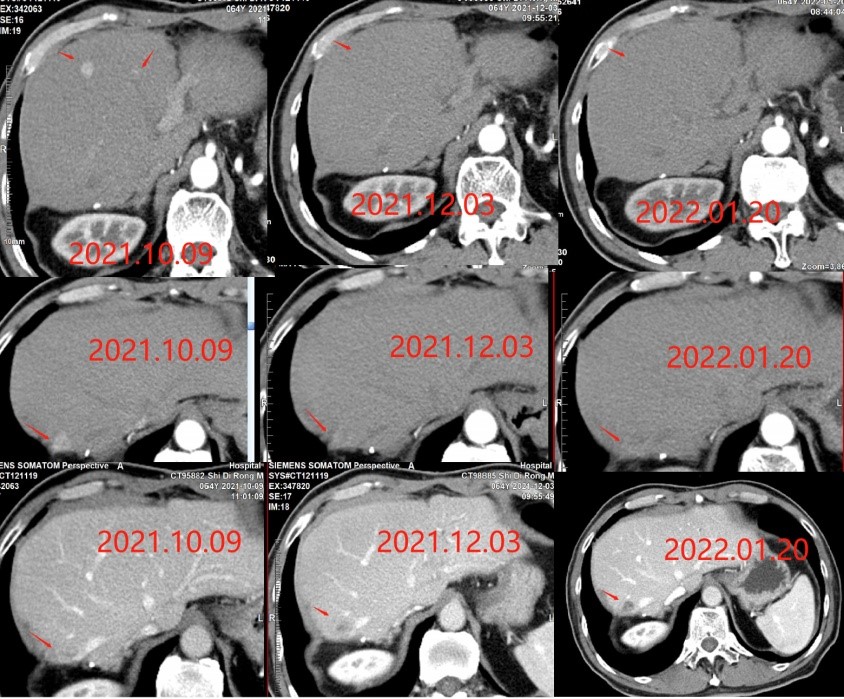

肿瘤科为史先生进行多个疗程靶向+免疫联合治疗后,影像资料显示:肝脏部分病灶消失,部分病灶强化减弱。史先生生活质量得到提高,临床症状明显好转。